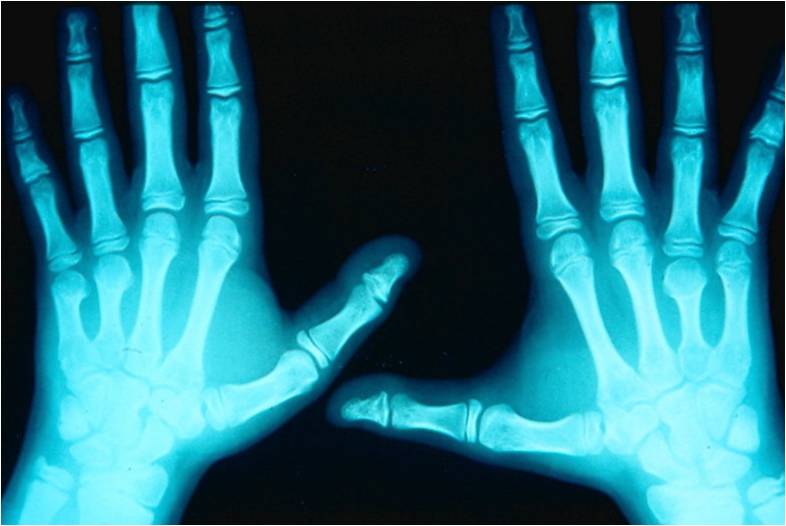

Brachydactyly presents with phalangeal, metacarpal, and/or metatarsal shortening or absence and may occur as an isolated trait or in combination with other anomalies. In isolated, non-syndromal, congenital forms, the inheritance is most likely autosomal dominant with a high degree of phenotypic variability. Brachydactyly may be associated with short stature, syndactyly, polydactyly, nail hypoplasia or aplasia, and a variety of malformation syndromes. Symphalangism, an autosomal dominant inherited disorder associated with symbrachydactyly or syndactyly, can be both the cause and effect of brachydactyly.54-56 Brachydactyly may also appear with either a longitudinal deficiency, such as radial and ulnar longitudinal deficiencies, or a transverse congenital amputation, such as constriction ring sequence and symbrachydactyly or transverse deficiency (Figure 11).57 It defines a malformation of the hand plate due to abnormal proximal-distal axis differentiation in the updated OMT classification.4

Figure 11. Brachydactyly. (Top left) Bilateral symmetric brachymesophalangia of the 4 ulnar digits and hypoplasia of the thumb’s proximal phalanx of the right hand are evident in a 14-month-old girl. There is an absence of the middle phalanx of the index finger and incomplete cutaneous syndactyly between the index and middle fingers of the left hand. The pediatric evaluation revealed no functional impairment or syndromal disorders. (Top middle and right) The clinical and radiographic appearance of a 52-year-old woman shows isolated bilateral and symmetric shortening of the third finger metacarpal. (Bottom left) Isolated unilateral involvement is evident in a 14-year-old girl with shortening of the right first metacarpal. (Bottom middle and right) A 40-year-old woman was diagnosed with brachymetacarpia of the left ring finger ray.